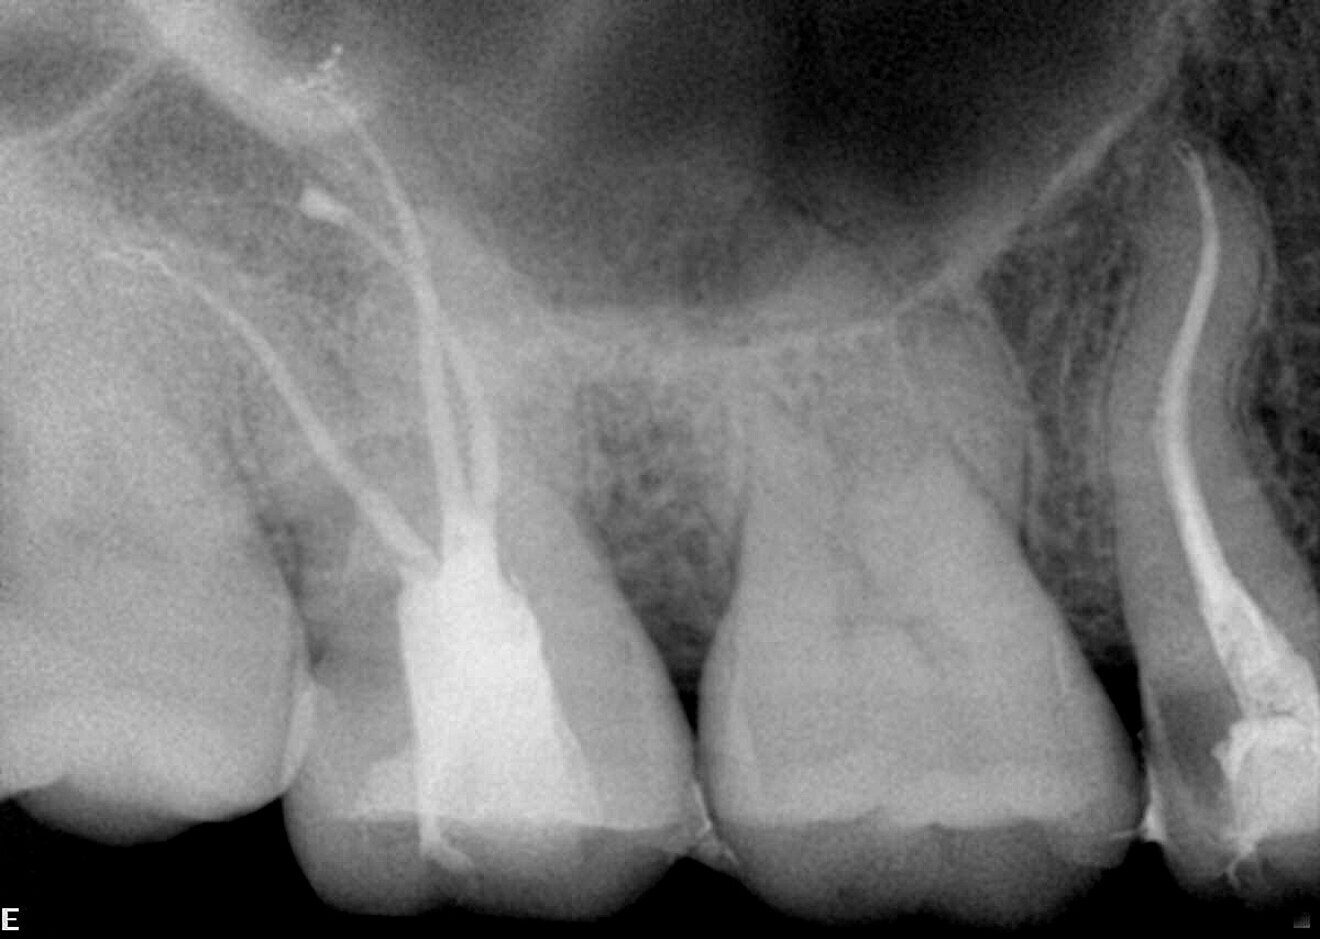

The preoperative radiograph of the premolar offers insight into the complex anatomy and multiple curvatures of the canals (Fig. 4). Two distinct canals are visible, yet they are so closely positioned that they could easily be misinterpreted as one. On the postoperative radiographs, the different apical foramina are clearly identifiable (Figs. 5 & 6). The images also show how well the file respected the original canal anatomy—shaping without excessive coronal enlargement to accommodate the multiple curves. No ledge formation or apical transportation had occurred.

Case 1—Fig. 4: Initial periapical radiograph.

Fig. 5: Post-op periapical radiograph.

ig. 6: Post-op periapical radiograph, angled view.